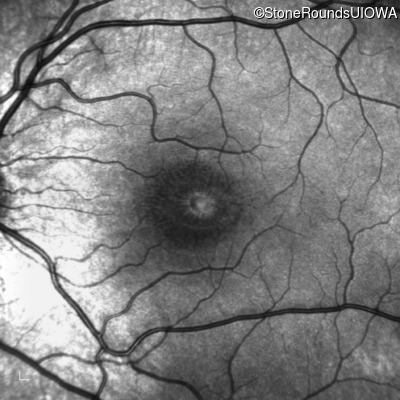

XL Retinoschisis (IIIB1)

XL Retinoschisis (IIIB1)

This 6 year old boy first experienced difficulty reading and seeing the blackboard at age 5.